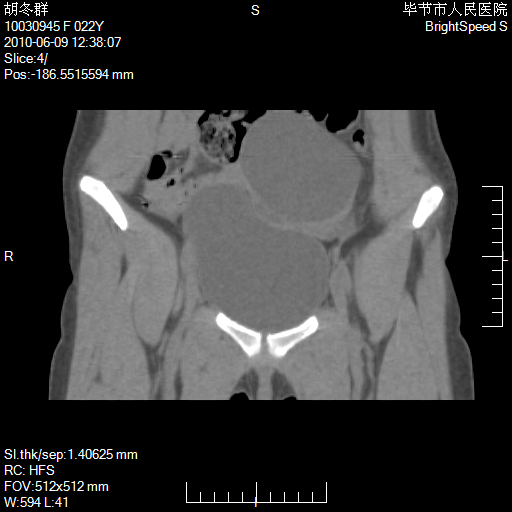

患者23岁,发现腹部包块3月。

盆腔内囊性占位;穿刺或者直接手术拿掉即可,不必紧张。

左侧卵巢囊腺瘤或囊腺癌

盆腔内囊性占位性病变;考虑左侧卵巢囊腺瘤。

有分隔、壁薄,支持考虑左侧卵巢囊腺瘤。

左侧卵巢浆液性囊腺瘤。

支持左侧附件区囊性占位,多考虑为囊腺瘤。

支持考虑左侧卵巢囊腺瘤;宫腔积液。

有分隔、壁薄,支持考虑左侧卵巢囊腺瘤。排尿后,膀胱缩小,由于重力作用,肿块下移就到了膀胱位置,很好理解。